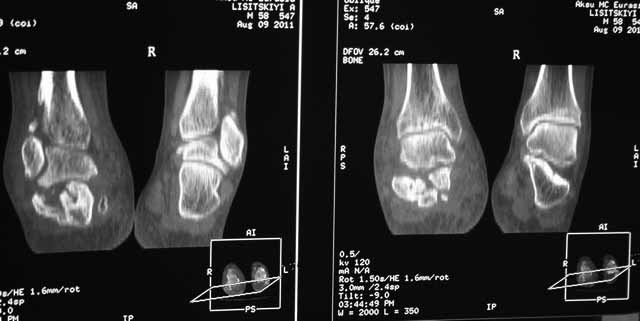

Данное исследование сделано в неправильной позиции стопы, стопа находится под прямым углом. Но несмотря на это, здесь можно увидеть, что латеральная стенка смещена, фиброз между фрагментами и варусное смещение пятки.

Топография зависит от позиции пятки в пространстве и неправильное положение закрывает обзор нужных структур. Важными структурами в исследовании пятки является задняя фасетка, бугор и боковые стенки. Существует специальные рентгенснимки, показывающие импинджмент с лодыжкой, а также положение бугра. Для КТ стопу надо инклинировать под 30 градусов, иначе можно пропустить важные переломы.

Кстати, Roy Sanders свою классификацию переломов пяточной кости обосновал на основании данных Компьютерной Томографии.

Нет срочности, но необходимо исправить варус и сделать субталарный артродез. Латеральное положение, расширенный доступ и closed wedge остеотомия с открытым кнаружи углом, возможно, удастся визуализировать через линию остеотомии недостающие части медиальной стенки - костный графт. Дистракция и после подготовки поверхности кости субталарный дистракционный артродез с помощью костного блока, взятого из крыла. Достаточно двух 6.5мм канюлированных шурупов из пяточного бугра медиально и латерально в направлении таранной кости. Из-за увеличения высоты стопы после артродеза кожа закрывается трудно, и могут быть краевые некрозы, которые лечатся долгими перевязками. Нужна предоперационная беседа по поводу задержки заживления, тогда больные встречают проблемы с пониманием.